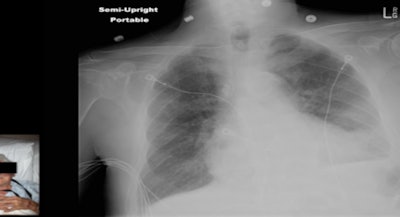

For the current study, the idea was to add a photograph that was inseparable from the patient's medical image, and the researchers also wanted to determine if the photographs were acceptable to the various providers involved in the patient care process. Technology developed at Emory embeds the photograph directly into the DICOM images using a camera installed on the x-ray system.

"When the x-ray tech triggers the machine, we get an x-ray from the patient and the camera gets a photo of the patient that includes the cassette ID plus the time stamp of the time the image was obtained," Sadigh. "All three -- the photo, the ID, and the time stamp -- go to a server and the server makes a DICOM image out of it."